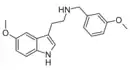

| 5-MT-NB3OMe [2] | artificial | 5-OCH3 | H | CH2C6H4(m-OCH3) | 5-methoxy-N-(meta-methoxybenzyl)tryptamine | 1648553-42-7 |